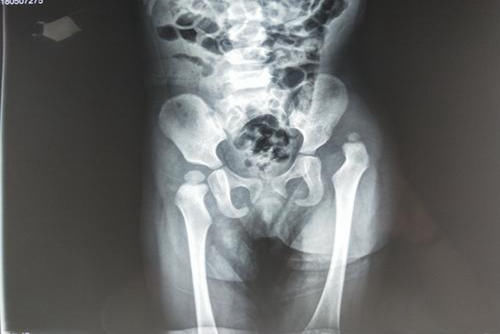

医生看到孩子腿上的臀纹,就建议宝妈去做个全面检查,可能是髋关节发育不良。果然,X光片中孩子腿部发育差异很明显,需要长期矫正治疗,否则会影响孩子正常走路。

其实,从孩子的臀纹是否对称,就能判断髋关节的发育状况。但是很多新手宝妈忽视了,认为宝宝臀纹不对称只是“屁蛋丑”,将来长大了就好了,还故意给孩子遮起来,唯独忽视了孩子身体的发育隐患。

一般情况下,宝宝两条腿的臀纹应该是对称的,数量和位置都差不多。如果臀纹不对称,可能是发育过程出了问题,最常见的就是髋关节发育不良。

据相关部门统计显示,我国新生儿中髋关节发育不良的占0.39%,北方比南方发生几率高,可能跟“绑腿”习俗有关。

髋关节发育不良,影响程度或轻或重,严重的会影响孩子的正常走路。所以,父母要学会鉴别孩子的臀纹,辨别出不正常的臀纹,及时就医治疗。